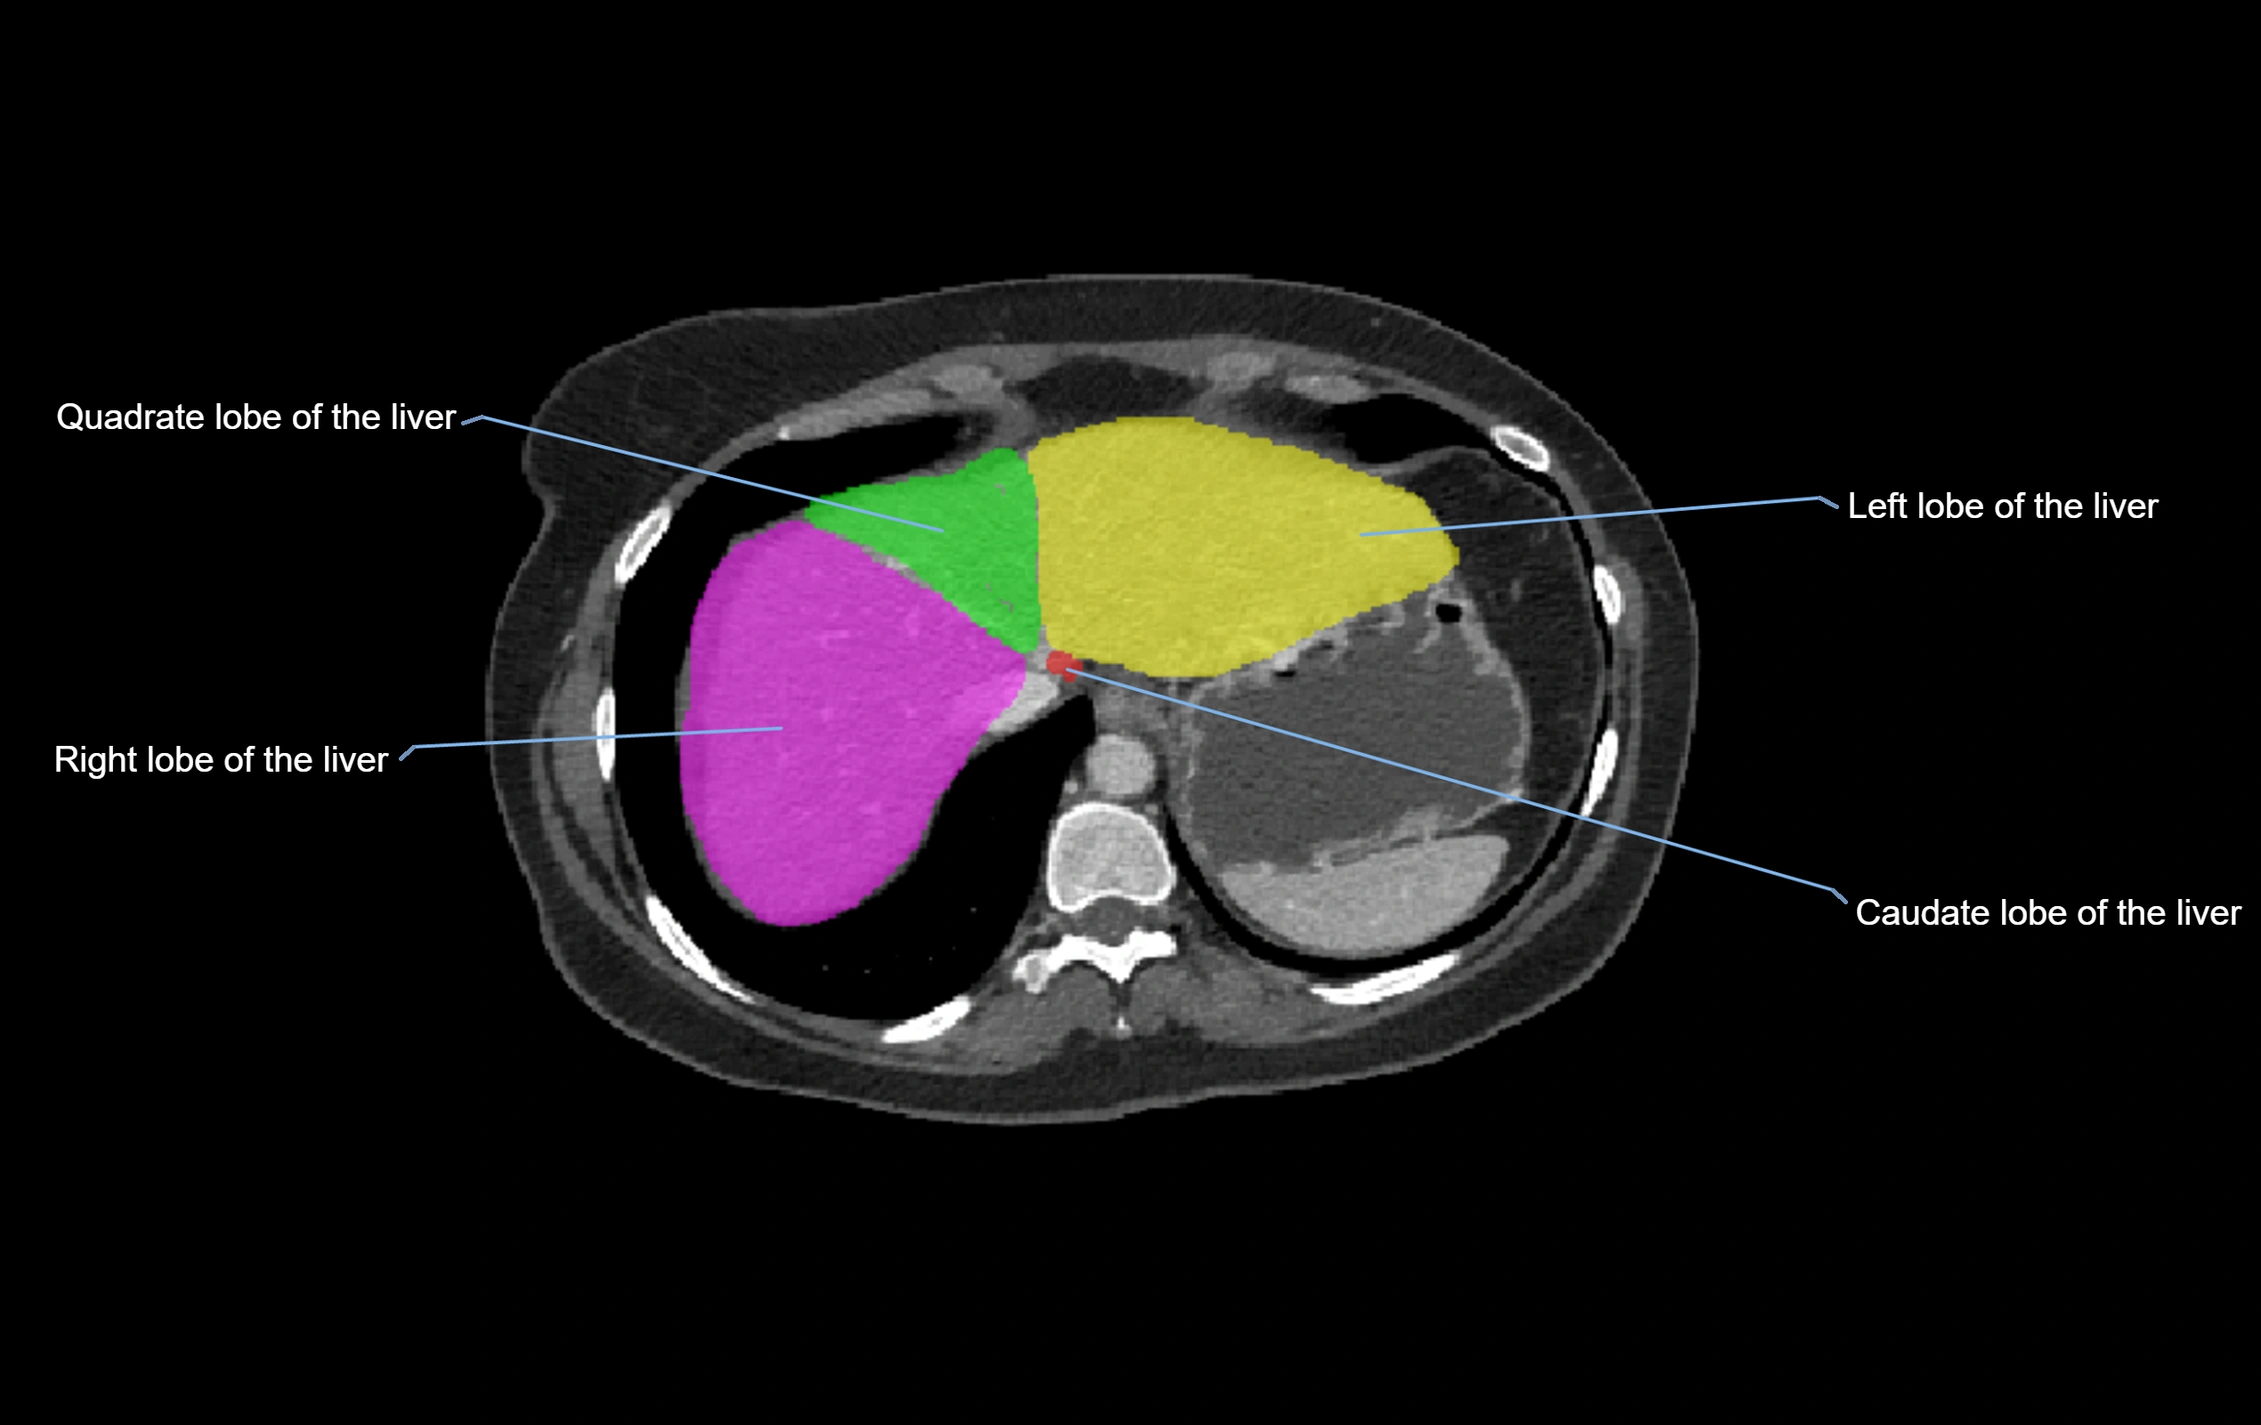

The caudate lobe of the liver is a distinct anatomical subdivision of the liver, designated as segment I in Couinaud’s classification. It lies on the posterior surface of the liver, between the fissure for the ligamentum venosum (left boundary) and the groove for the inferior vena cava (IVC) (right boundary). Superiorly, it is related to the posterior liver surface, and inferiorly it is separated from the left lobe by the porta hepatis.

The caudate lobe is unique because it receives dual portal venous and arterial inflow from both the right and left portal veins and hepatic arteries. It also has independent venous drainage directly into the IVC via multiple small hepatic veins, unlike other lobes that drain through the three main hepatic veins.

CT Image

image